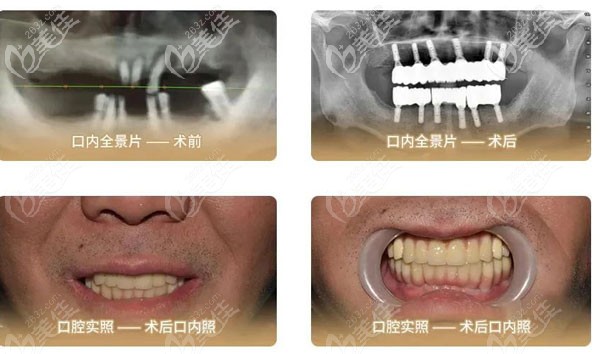

(这是刘叔叔做全口种植牙前后的口腔照) ↑

栗伟医生决定运用3D数字化导板,配合e+立得用数字化种植牙技术为刘叔叔上下各植入6颗种植体,来稳固恢复其全口牙的咀嚼功能。